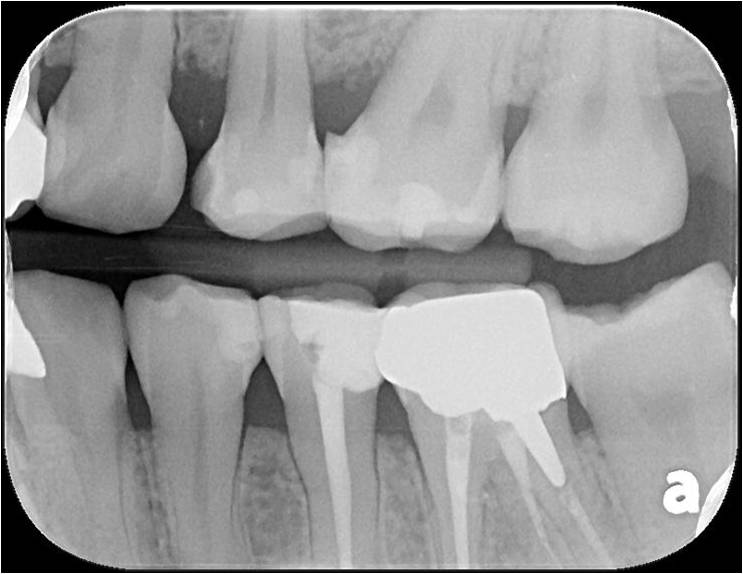

二次蛀牙,牙髓未受侵犯

崁體窩洞製備